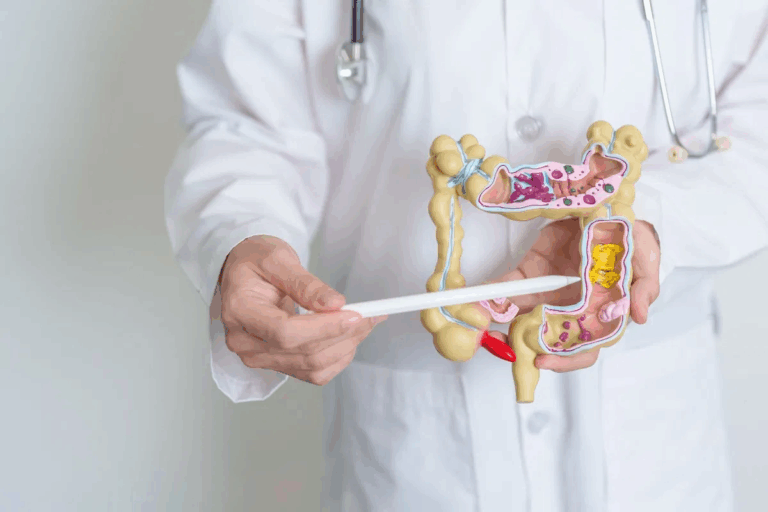

The Pathophysiology of Acute Coronary Syndrome

It’s important to know how acute coronary syndrome works to help patients quickly. ACS happens when the heart muscle doesn’t get enough blood. This usually happens because of a blockage in the coronary arteries.

Atherosclerosis and Plaque Rupture

Atherosclerosis plays a big role in ACS. It’s when fatty deposits, or plaques, build up in the heart’s arteries. If a plaque bursts, it can cause a blood clot. This clot might block blood flow to the heart.

Atherosclerosis gets worse over time. It can be caused by high blood pressure, high cholesterol, and smoking.

Coronary Thrombosis Formation

When a plaque bursts, it exposes blood to a very sticky material. This can start a blood clot in the coronary artery. This clot can block the artery, causing myocardial ischemia or infarction.

The clotting process is complex. It involves platelets getting active, sticking together, and starting the coagulation cascade.

Myocardial Ischemia and Infarction Process

Myocardial ischemia happens when the heart doesn’t get enough blood. This means it can’t get enough oxygen. If this goes on for too long, it can cause a heart attack.

Understanding how ACS works is key to treating it right. Knowing the pathophysiology helps doctors give the best care. This can lead to better outcomes for patients.